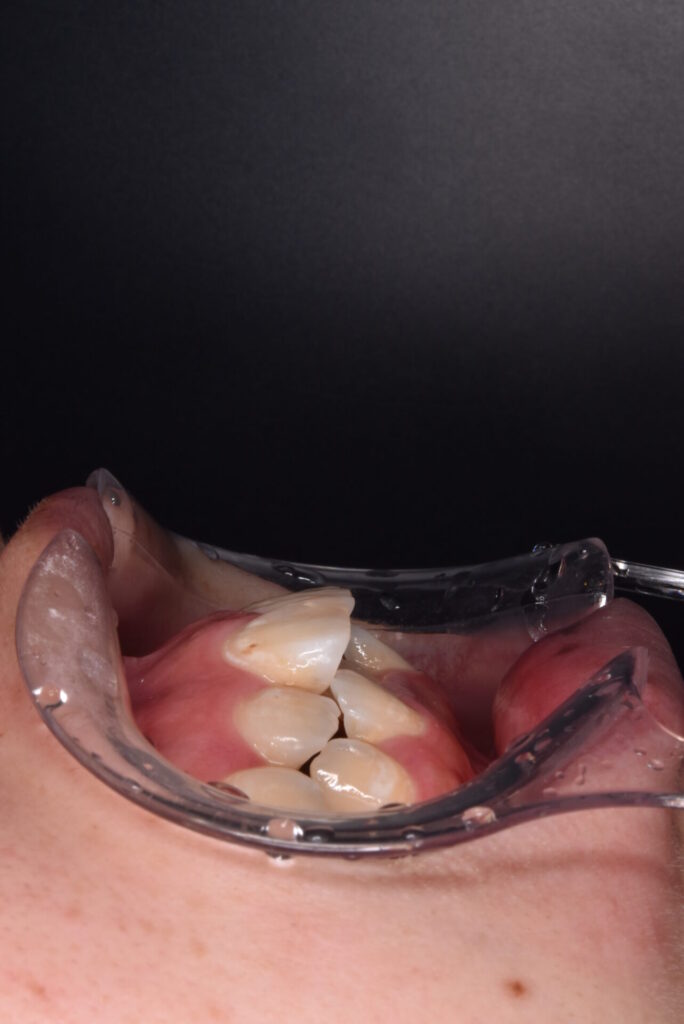

矯正前

前歯の突出感と下の歯の叢生が目立ちます。